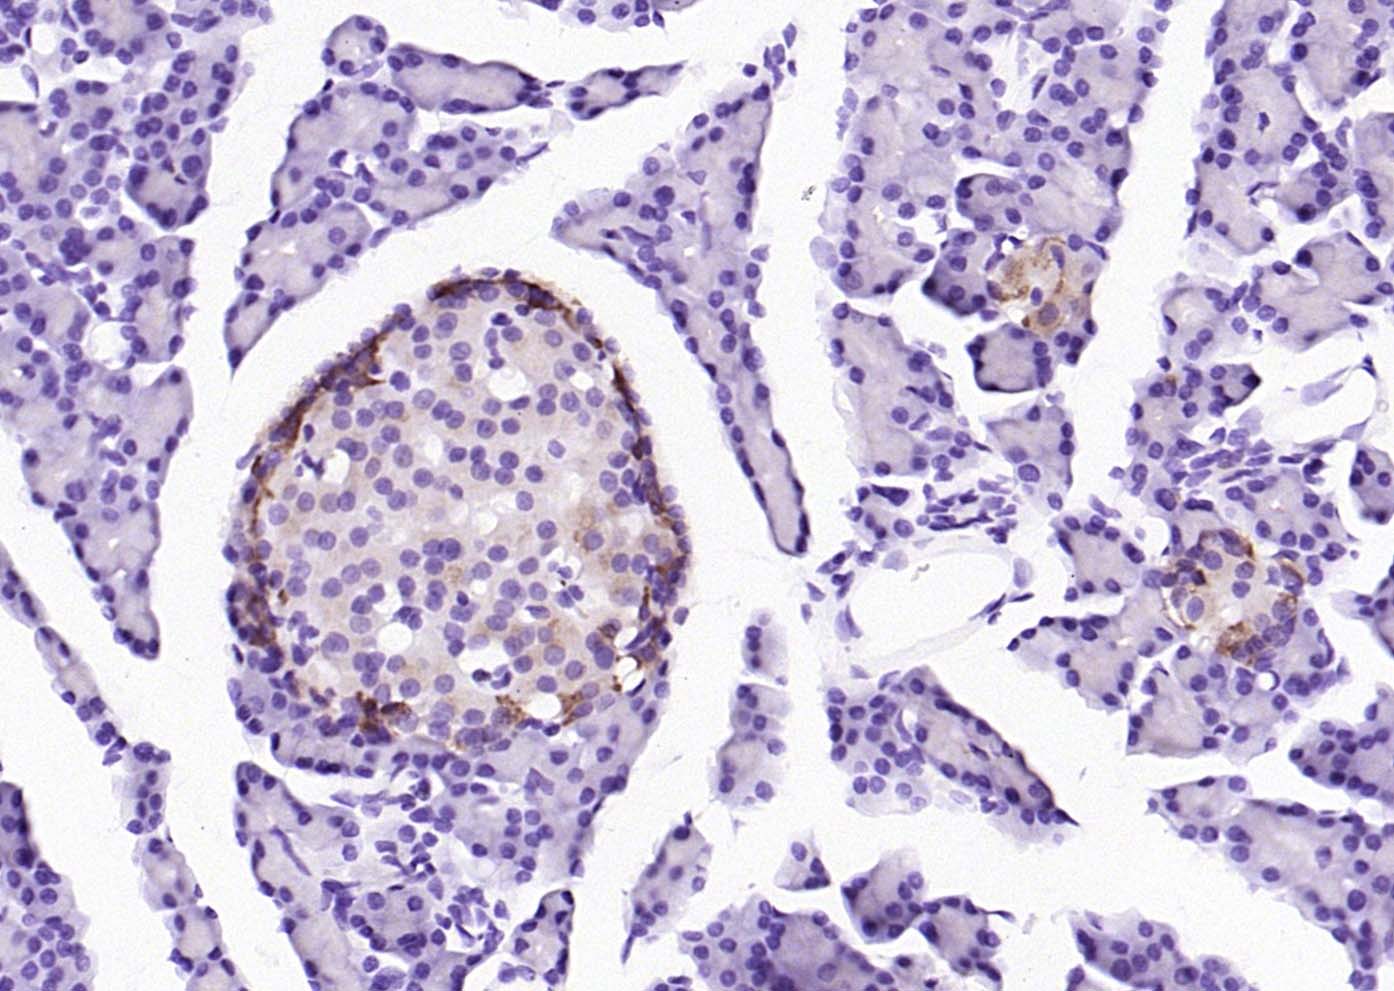

| IHC-P | Human, Mouse, Rat | Rabbit, Pig, Cow, Dog | 1:100-500 |

| IHC-F | Human, Mouse, Rat | Rabbit, Pig, Cow, Dog | 1:100-500 |